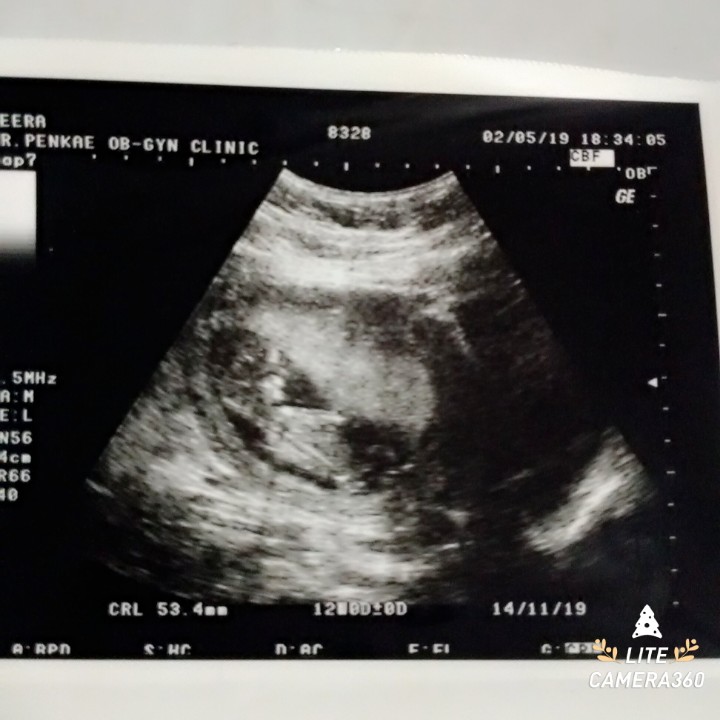

ตอน12 วีคค่ะ

ตอน 3 เดือนค่ะ